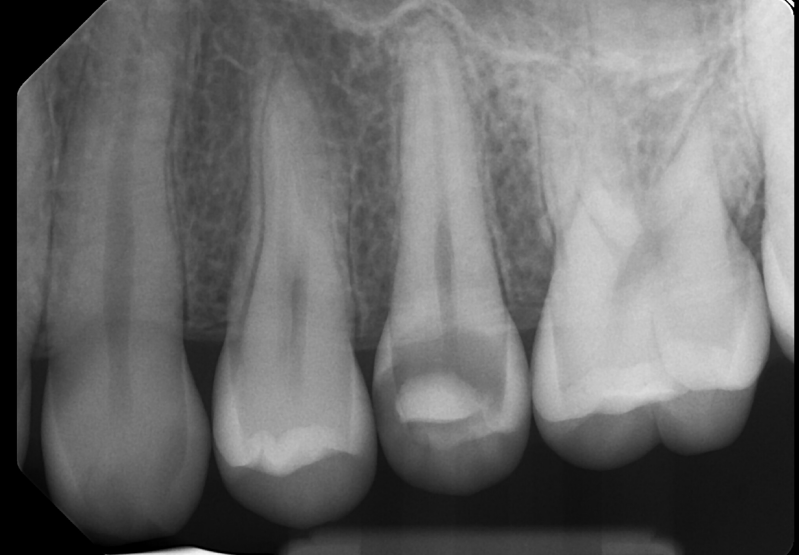

Case: RCT on Tooth #9

67-year-old male, diabetes, no known drug allergies.

Dx: Pulp necrosis and chronic apical abscess.

Tx: Root canal therapy.

Reflection

The main challenge in this case was negotiating calcified canals through an existing crown. Locating the orifice was difficult, but persistence paid off. The final X-ray showed a sealer puff from an accessory canal—right where the sinus tract had traced—suggesting thorough cleaning. With proper disinfection, we’re hopeful this will lead to healing of the fistula. The sealer puff is evident and, given its biocompatibility, not a major concern, though follow-up is essential.